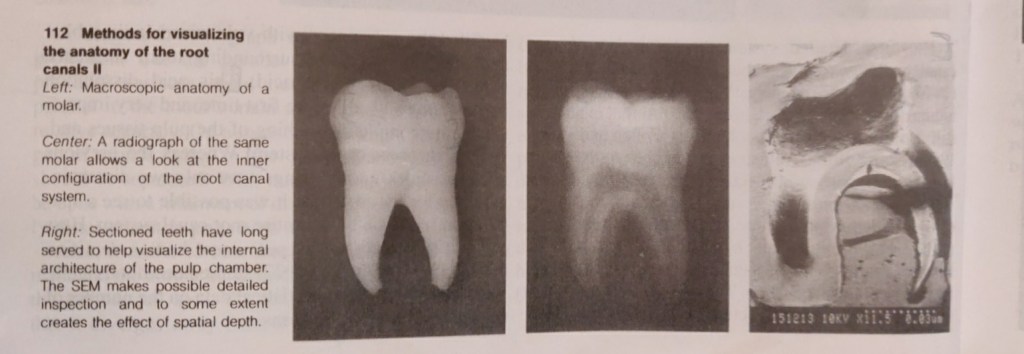

Hession (1977a-d) showed the shape of the root canal system radiographically before and after in vitro treatment. The abundant range of research tools is complemented by in vivo radiographs, microradiographs, scanning electron microscopy (SEM), computer reconstructions, monographs of individual cases, and many other aids (Baumann 1995). Subsequently, an immense body of facts has been accumulated and these are presented in excellent didactic style in books,videos, slide series, reports, seminars, and demonstration. This new information should be offered in further education courses (Baumann 1994, 1955).